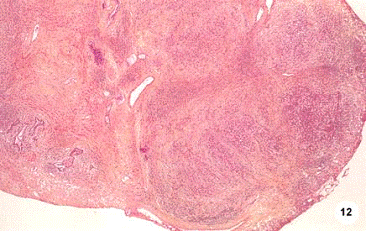

Рис. 12

Неспецифический гранулематозный простатит. Тканевая архитектура предстательной железы исчезает, дольчатые воспалительные инфильтраты.